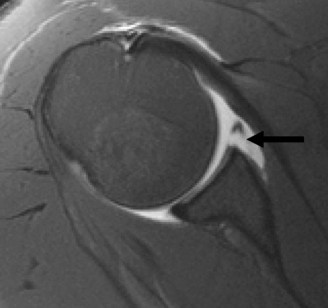

The correct answer is (A). The MRI demonstrates an HAGL lesion. The MR arthrogram shows fluid extending down the medial humerus and is indicative of an HAGL. Most commonly, with an anterior dislocation, the anterior band of the inferior glenohumeral ligament is torn. With a posterior dislocation, the posterior band is torn creating a reverse HAGL. The ligament tends to tear off the humeral side. These are important injuries to identify as arthroscopic labral repair and capsular shift may be unsuccessful without concomitant repair of the HAGL lesion. Many authors advocate an open approach to repair an HAGL lesion.